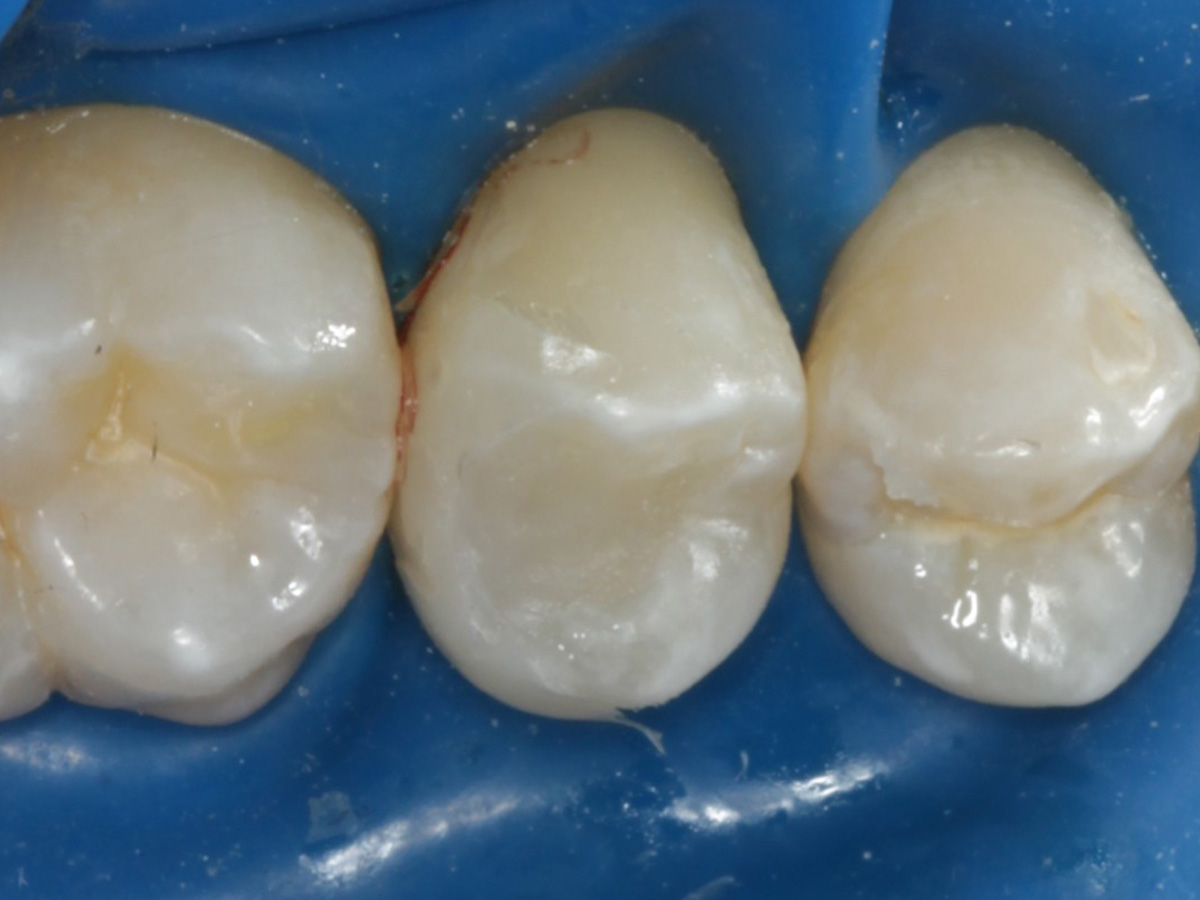

Kavität gefüllt (Injektion Moulding: Flowkomposit, erwärmtes Seitenzahnkomposit aus Karpule)

Abbildung 22

Matrize und Twinring entfernt;  weitere Lichthärtung von bukkal und oral